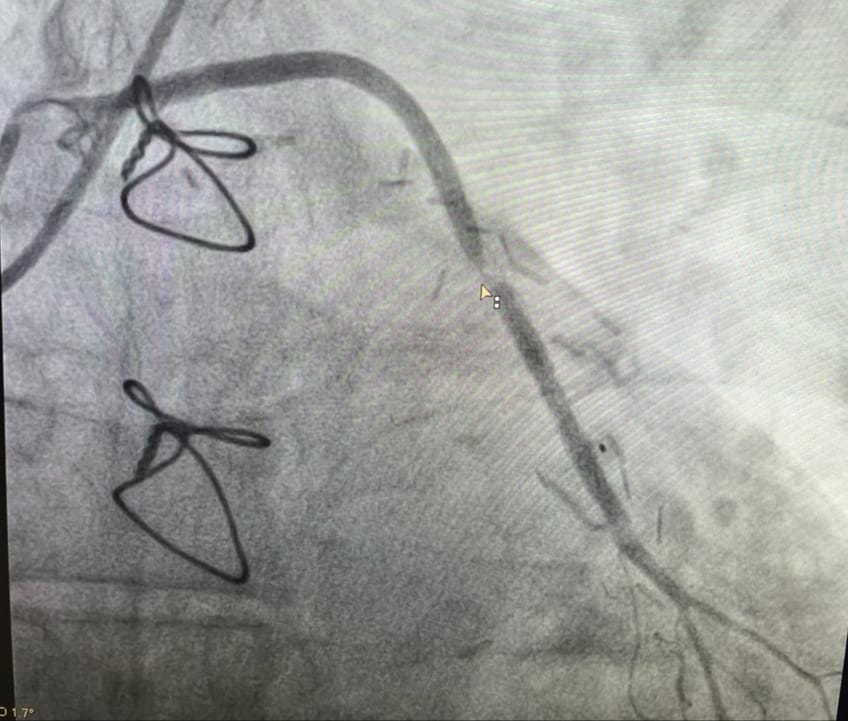

Липецкие хирурги сосудистого центра БСМП №1 провели уникальную для региона операцию на коронарной артерии. Об этом сообщает областное управление здравоохранения. Раньше такие сложные операции делали только в федеральных центрах.

Как пояснили в управлении, в больницу попал с пациент с жалобами на боль в груди. После коронарошунтографии стало понятно, что у него возникли проблемы со стентом, который ранее имплантировали в шунт.

Исходя из данных клиники при СПбГУ, шунт — это обходной маршрут для крови мимо поврежденной артерии, который хирурги создают из вен и артерий пациента, а стент — специальный каркас, который вводят в сосуд для его расширения.

— В результате было принято решение провести операцию, благодаря которой был поставлен стент с лекарственным покрытием в ранее стентированный шунт, — отметили в управлении здравоохранения.

В итоге через 3 часа после операции пациент вернулся к прежней двигательной активности, а боли в груди перестали его беспокоить.